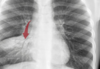

13

Q

¿Signo de la silueta?

Ubicación:

A

Positivo

Lóbulo superior